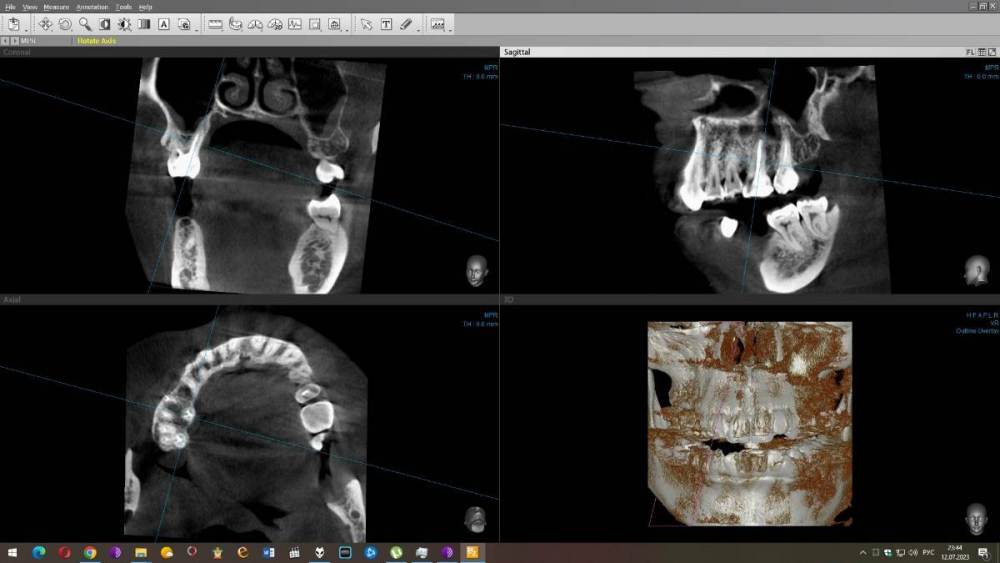

Carioznik Опубликовано 10 июля, 2023 Поделиться Опубликовано 10 июля, 2023 (изменено) образ диска с Вашим КТ - не открывается (поврежден). Либо создан с ошибкой, либо не загрузился нормально. Можно просто все папки на диске заархивировать и закачать. Хотя, думаю, уже пора новое КТ делать и разбираться на его основе. Изменено 10 июля, 2023 пользователем Carioznik Ссылка на комментарий

wladdX Опубликовано 12 июля, 2023 Поделиться Опубликовано 12 июля, 2023 Исследование от 27.12.2021. Лучше бы поновее Ссылка на комментарий

Carioznik Опубликовано 13 июля, 2023 Поделиться Опубликовано 13 июля, 2023 по этому старому КТ: на 16 - есть пропущенный канал, от этого, на одном из корней - есть небольшой воспалительный процесс (на тот момент). "Само не заживет", будет только расти, может, на сегодняшний момент - уже стал большой). Но жалобы в таких случаях обычно другие. Делайте новое КТ (по старому только гадать...) и снова, очный осмотр стоматолога, явно понадобится. 1 Ссылка на комментарий